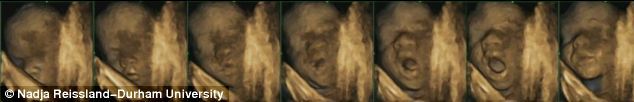

Dr. Reissland şi colegii ei de la Durham University au folosit aşa-numita ecografie 4-D – imagini ecografice 3-D care pot fi văzute în timp real – pentru a realiza imagini a 8 fetiţe şi 7 băieţi, în fiecare lună a sarcinii, între a 24-a şi a 36-a săptămână de sarcină.

În stadiile mai timpurii ale sarcinii, cercetătorii au putut observa cum bebeluşii îşi atingeau partea superioară şi părţile laterale ale capului, iar mai târziu treceau şi la atingerea părţilor inferioare, mai sensibile, ale feţei şi gurii.

Până în săptămâna a 36-a, majoritatea copiilor deschideau gura înainte de a şi-o atinge – un semn că anticipau atingerea. La copiii sănătoşi, sensibilitatea zonei din jurul gurii creştea pe măsură ce se dezvoltau, ceea ce ar putea însemna că ei deveneau mai conştienţi de mişcările gurii. Oamenii de ştiinţă cred că o anumită succesiune de mişcări, precum deschiderea gurii înainte de sugerea degetului, arată că la copil se dezvoltă deja intenţia, executarea unei mişcri cu un anumit scop.